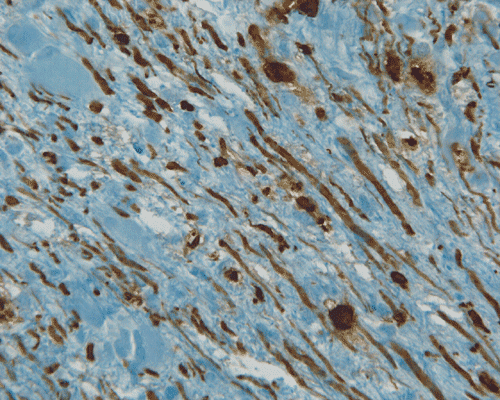

P. NFP |

Panel A to E are MR images. Panel F and G are taken from intraoperative cytologic preparation. Panel H to M are taken from frozen section. Panel N and O are from paraffin section. These sections are stained by hematoxylin-eosin stain. Panel P is immunohistochemistry for neurofilament proteins. Panel Q is stained by Luxol fast blue-Periodic acid Schiff (LFB-PAS) stain.

Pathology of eosinophilic myelitis

Eosinophilic myelitis is featured by lymphocytic infiltration accompanied by a varying intensity of eosinophils. Both the myelin and axons may be damaged. Axonal spheroids can be seen and indicate primary axonal damage rather than secondary damage following demyelination 14, 15. Destruction of axons in the lesion may well explain the relatively poor recovery of this condition. There is increase in eosinophils in CSF in the our under discussion. However, the CSF studies are normal in two previous studies 14, 15.

The eosinophils play an important role in causing the damages. Infiltration by eosinophils and depositions of activated products of eosinophils are commonly seen in atopic disorders, such as atopic bronchial asthma, allergic rhinitis and atopic dermatitis. The presence of atopic diathesis as well as eosinophilic cationic protein deposition suggests that atopy may represent one of the risk factors for developing eosinophilic myelitis. Eosinophilic cationic protein is one of the neurotoxic proteins released by activated eosinophils Eosinophil cationic protein and other products of eosinophils such as major basic protein have been shown to be neurotoxic. The infiltrating eosinophils may therefore well contribute to the neural damage.

In addition to eosinophils, predominant CD8 T-lymphocytes infiltration is commonly observed 14. Selective infiltration of CD8 T-lymphocytes into the parenchyma, may suggest the critical pathogenic role of these cells, such as a cytotoxic role rather than a secondary suppressive one. In atopic disorders, acute lesions are characterized by predominant CD4 T-lymphocytes infiltration over CD8 T-lymphocytes infiltration, while CD8 T-lymphocytes predominate in chronic lesions. Therefore, the predominant infiltration of CD8 T-lymphocytes seen in the spinal cord may reflect the chronic nature of the lesions.